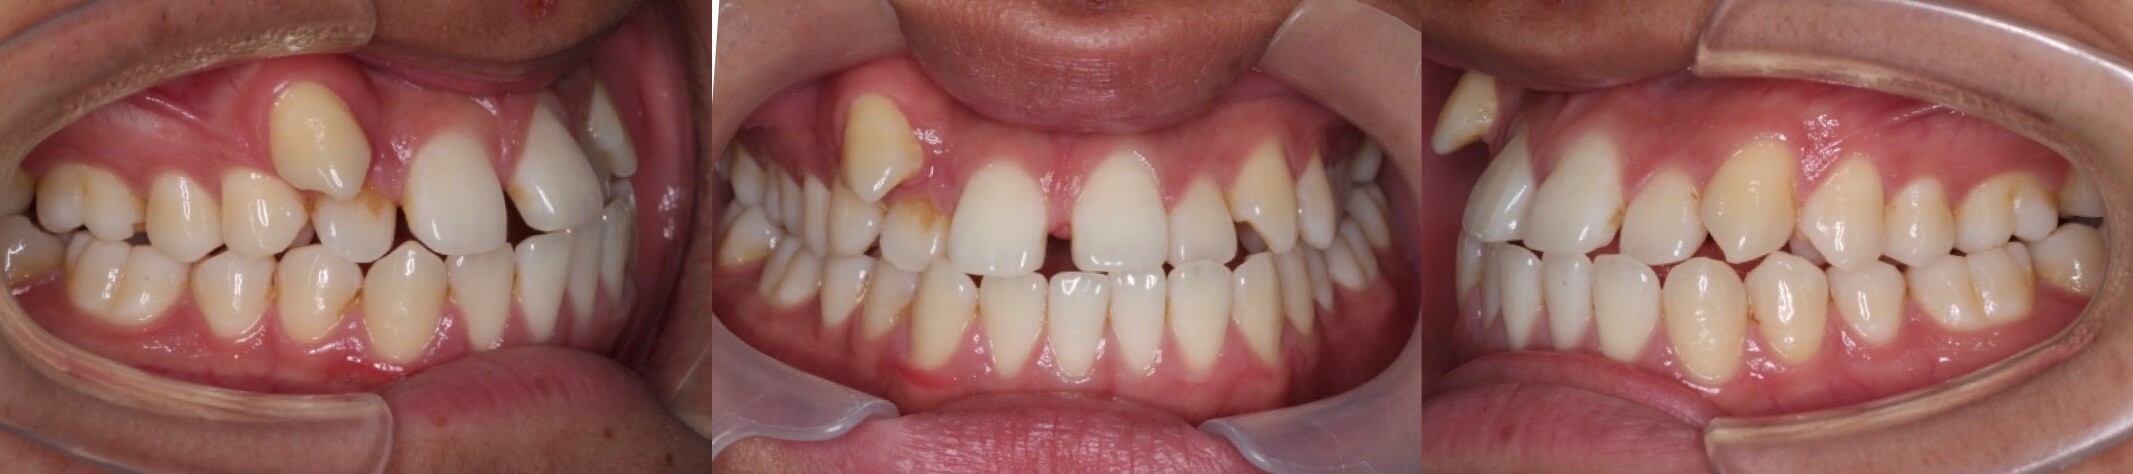

大学生女性・唇側矯正装置・小臼歯4本抜歯

<顔のビフォーアフター>

<症例概要>

主訴:受け口・前歯のガタガタ

年齢・性別:大学生女性

住まい:千葉県八千代市

症状:反対咬合・重度叢生・開咬

治療方針:上下小臼歯抜歯・空隙閉鎖

治療装置:唇側矯正装置

固定装置:上バイヘリックス装置・III級顎間ゴム

抜歯:上第二小臼歯・下第一小臼歯・下親知らず(計6本)

治療期間:2年2か月

リテーナー:上下フィックスタイプ+クリアタイプ

治療費用:968,000(税込)

代表的副作用:痛み・治療後の後戻り・歯根吸収・歯髄壊死・歯肉退縮

歯が並ぶスペース不足が大きく、前歯の不揃いが強いケースです。また、上下の前歯は開咬状態になっており咀嚼障害もあります。上下小臼歯抜歯を行いできたスペースをうまく利用して前歯を並べ、III級顎間ゴムを使用し下の歯列全体を親知らずを抜歯した後方へ起こしました。非常に難しい治療方針でしたが、ご本人がゴムの使用を頑張ってくれたので予定より早く治療期間も終わり、審美的にも機能的にも良い歯並びになりました。